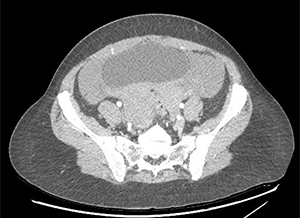

There is a large hemoperitoneum (arrow below) with a massive rectouterine structure (star below) concerning for clot.

Management of ruptured ovarian cysts is usually conservative (i.e. supportive, observation) unless the patient has hemodynamic instability or ongoing or heavy blood loss. In these cases, the treatment is surgical with removal of blood and cyst if visible.

This patient developed hypotension in the ED her hemoglobin dropped 2.5 points in 2 hours. She was taken urgently to the OR and had 1 liter of blood removed. She was discharged in stable condition later that day.